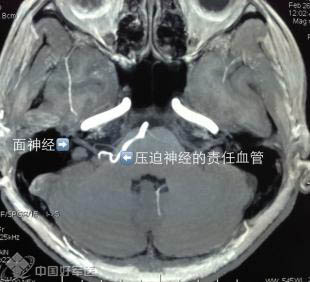

空军总医院神经外科周岩副主任医师的手术日记中国好声音选手金志文有一首歌的歌词写的是“眼皮跳跳,好事快来到”。可是漂亮的肖女士的眼皮